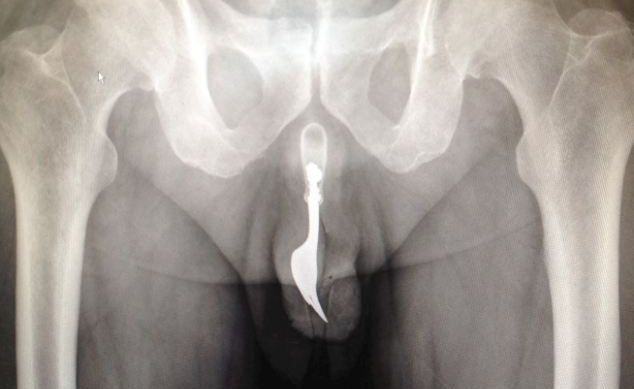

Bild: International Journal Of Surgery